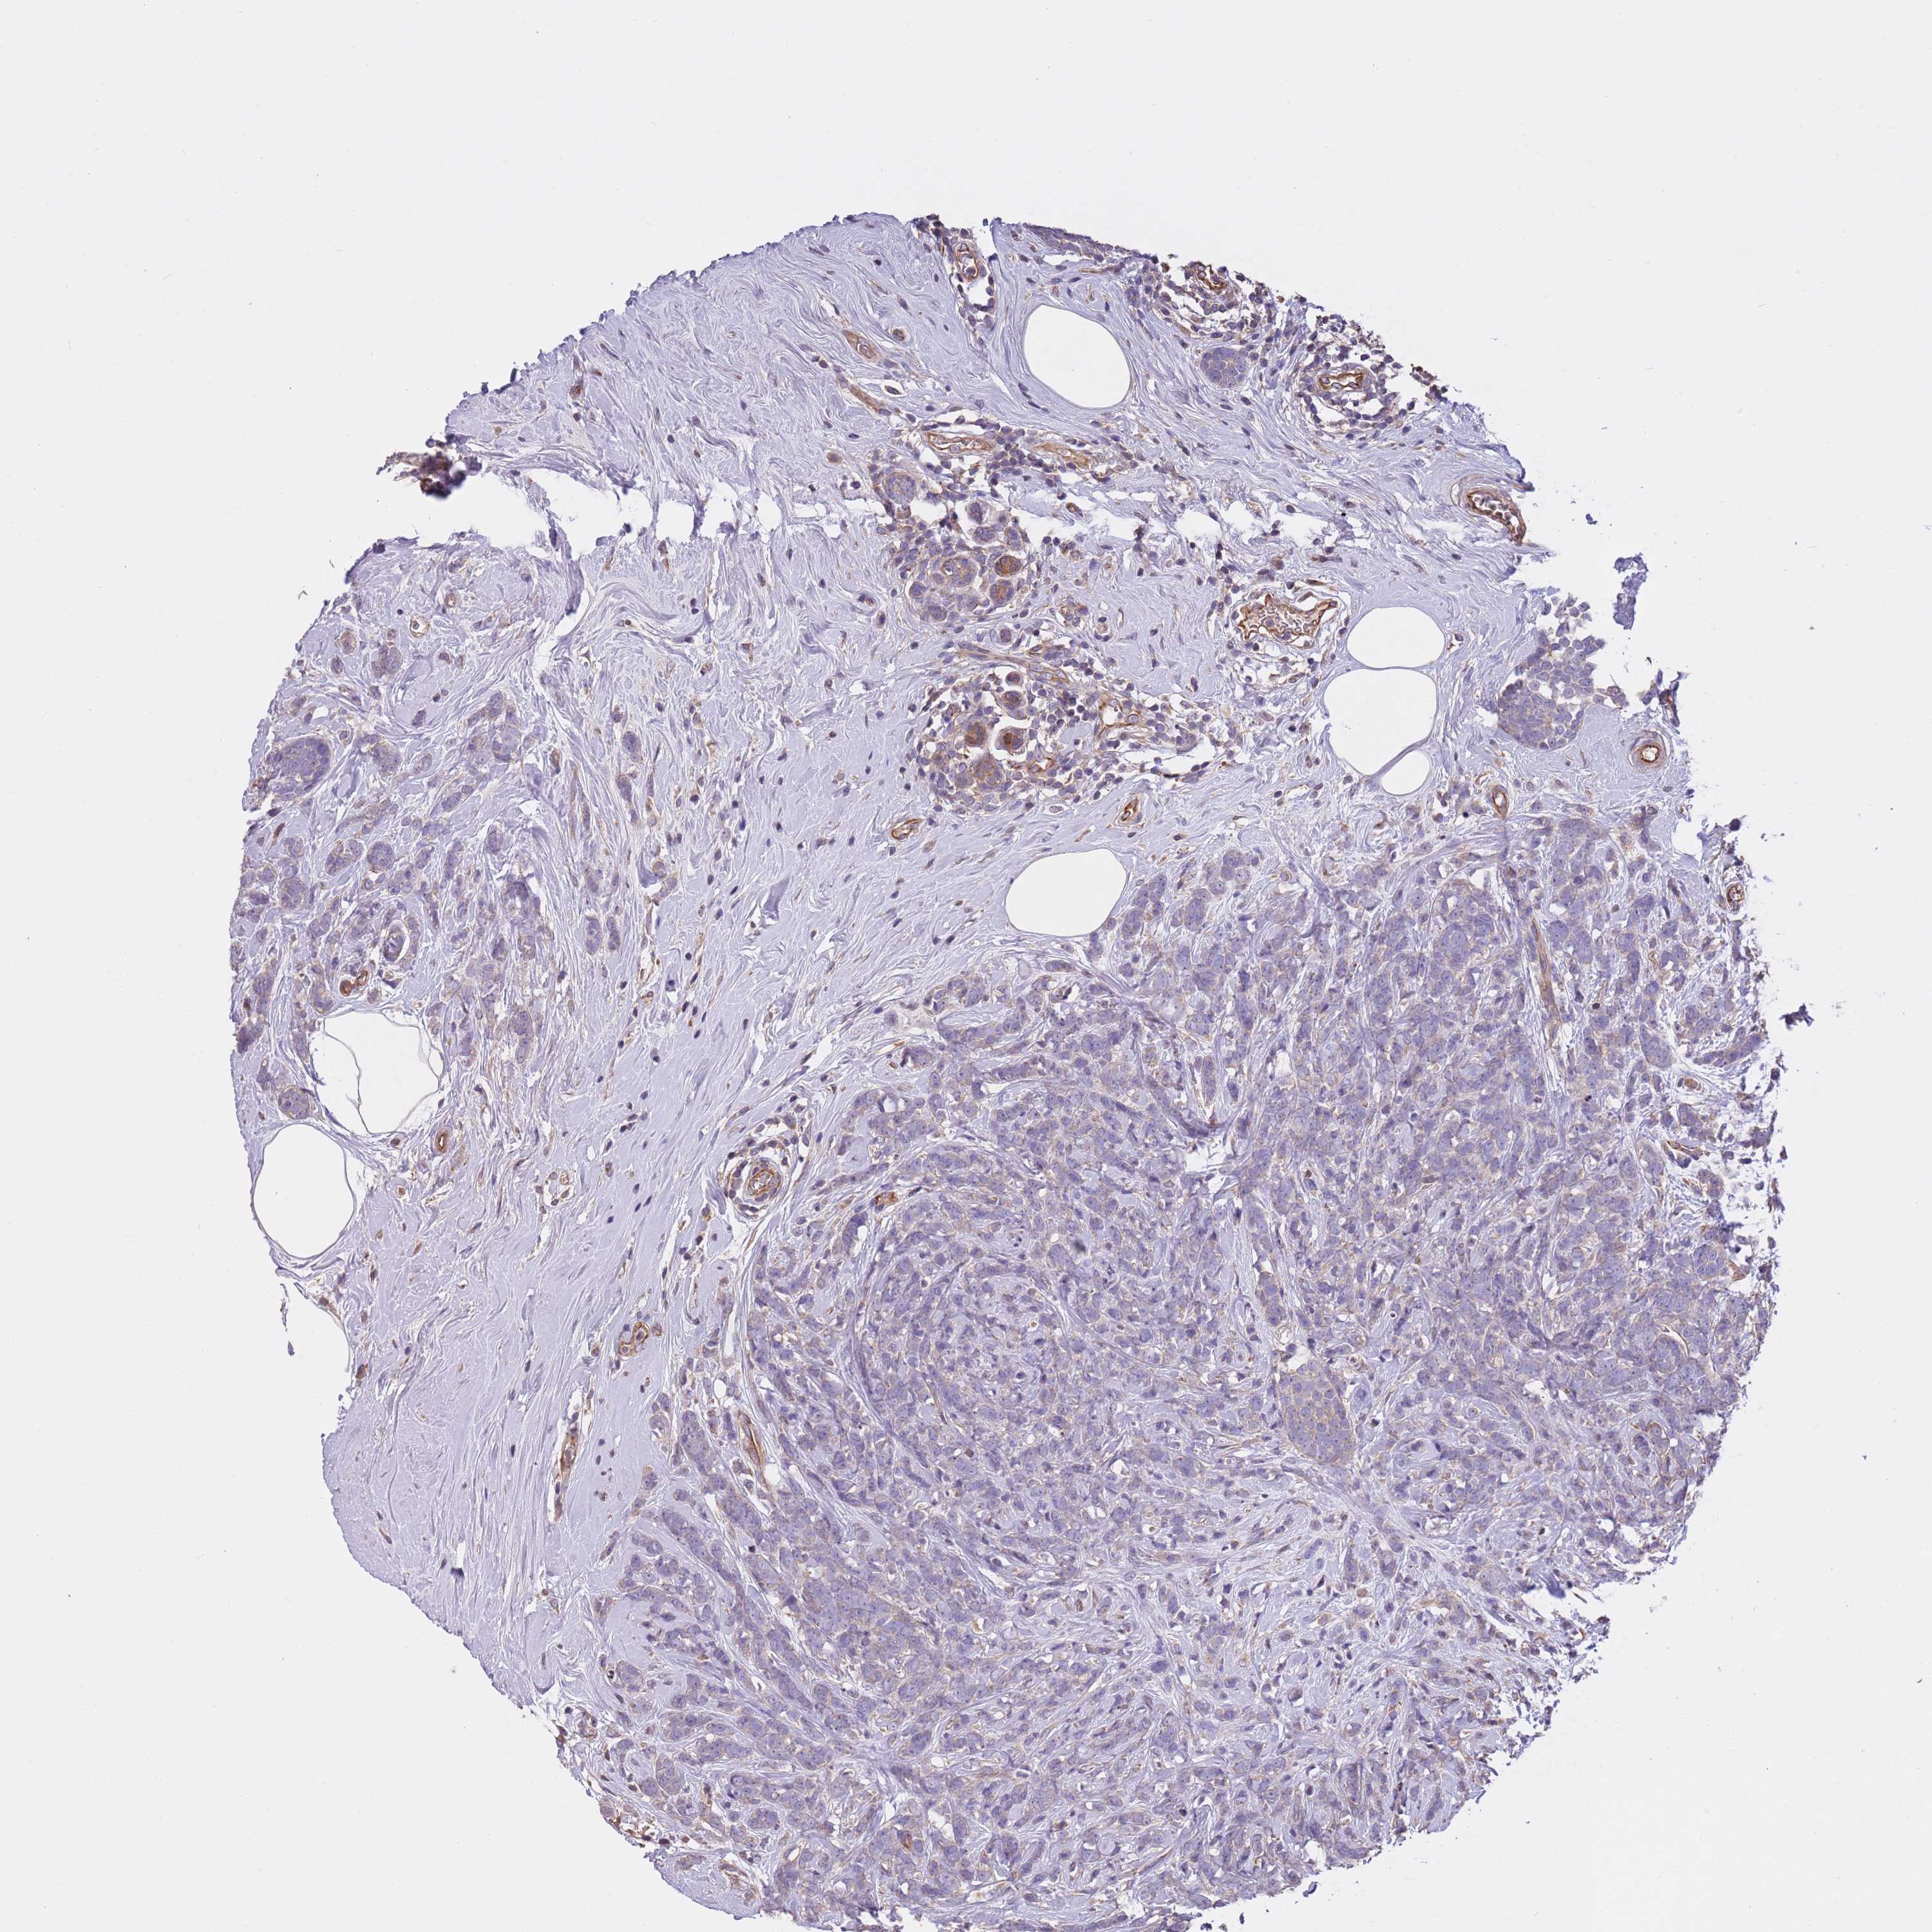

CANCER BREAST CANCER Show tissue menu

BRCA TCGA BRCA VALIDATION PROTEIN EXPRESSION

Breast cancer

Human cancer

Breast invasive carcinoma